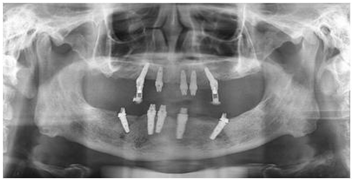

宁德中富口腔种植科医生对李大爷的口腔情况进行系统检查后,诊断李大爷为重度牙周病导致全口牙齿缺失。由于李大爷牙齿缺失时间较长,导致牙槽骨严重萎缩,故拟定人工植骨后三个月,采用微创口腔种植。

人工植骨三个月后,骨量达到种植标准。主治医生在上下颌共植入8颗种植体。医生为李大爷取模,制作临时牙。